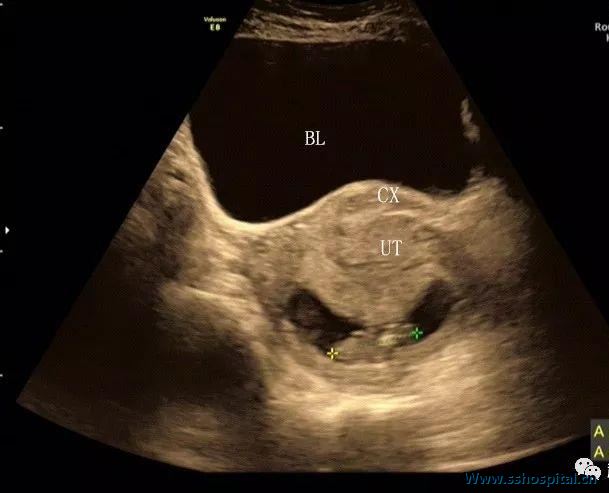

膀胱显著充盈,壁完整光滑,腔内未见异常回声。

子宫呈极度后倾后屈位,宫颈管细长;宫体位于宫颈后方,宫底平宫颈外口水平;宫腔内可见狭长型胎囊,大小 59×18 mm,内见胚胎约 34 mm,并见胎心搏动及卵黄囊(图 1 和图 2)。

超声提示:宫内早孕,约孕10周;子宫形态超声改变,考虑妊娠子宫箝闭;尿潴留。

图 2 下腹部横切面示宫颈(CX)位于膀胱(BL)与子宫体(UT)之间,宫腔内妊娠囊及胚胎均受压